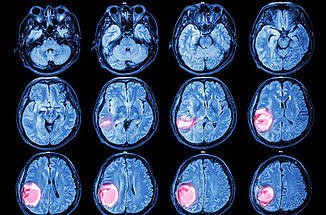

Cáncer cerebral o Cáncer de sistema nervioso central (SNC) es un grupo de células anormales que crece y se multiplican en el

cerebro o alrededor de él. Los tumores pueden destruir directamente las células sanas del

cerebro. También pueden dañarlas indirectamente por invadir otras partes del cerebro y causar

inflamación, edema cerebral y presión dentro del cráneo. Los tumores cerebrales se clasifican

según diferentes factores, como el lugar donde se encuentran o los tipos de células que

involucran y pueden ser benignos o malignos, dependiendo de la rapidez de su crecimiento y

de la posibilidad o no de curarse definitivamente después de los tratamientos.